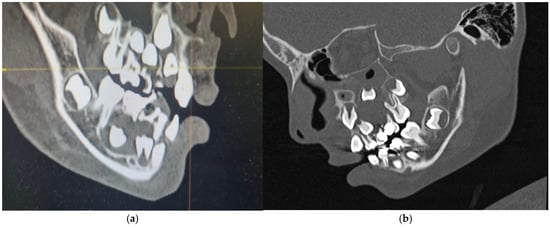

The orthopantomogram, brought by the patient, presented unycistic radiolucency with well-defined margins on the mandible’s right side as well as the left side of the maxilla. A multi-slice computed tomogram (MSCT) showed a cystic lesion in the maxilla extending from the second left permanent incisor to the first permanent molar. It included the unerupted follicles of the permanent canine, first, and second premolar, and was separated from the maxillary sinus by a thin bone. A second lesion was observed in the mandible, extending from the primary right canine to the first permanent molar. It also involved the crowns of the unerupted permanent teeth [Figure 5a,b].

Figure 5. Preoperative MSCT of a nine-year-old boy showing unicystic radiolucencies on the right side of the mandible (a) and left side of the maxilla (b).